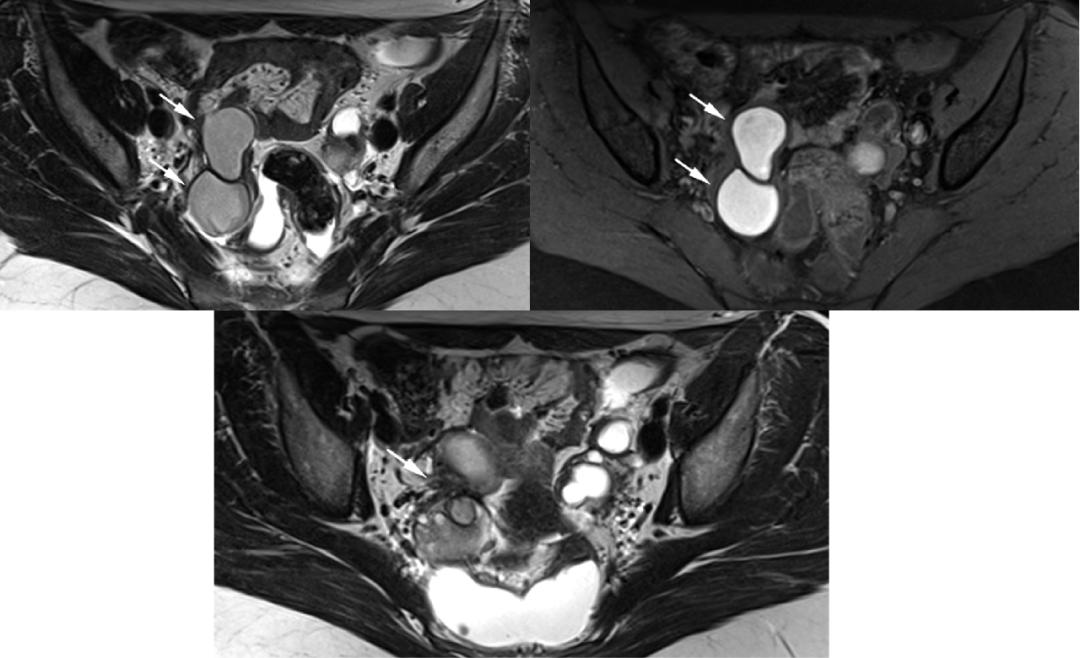

CASE 2

子宫内膜异位至左侧输尿管下段,T2WI 轴位和矢状位子宫颈左旁结节样低信号,边缘呈不规则星芒状,左侧输尿管扩张。

CASE 3

子宫内膜异位至直肠系膜,T2WI 轴位阴道左后方低信号结节,边缘星芒状,累及直肠系膜,但未累及直肠壁。